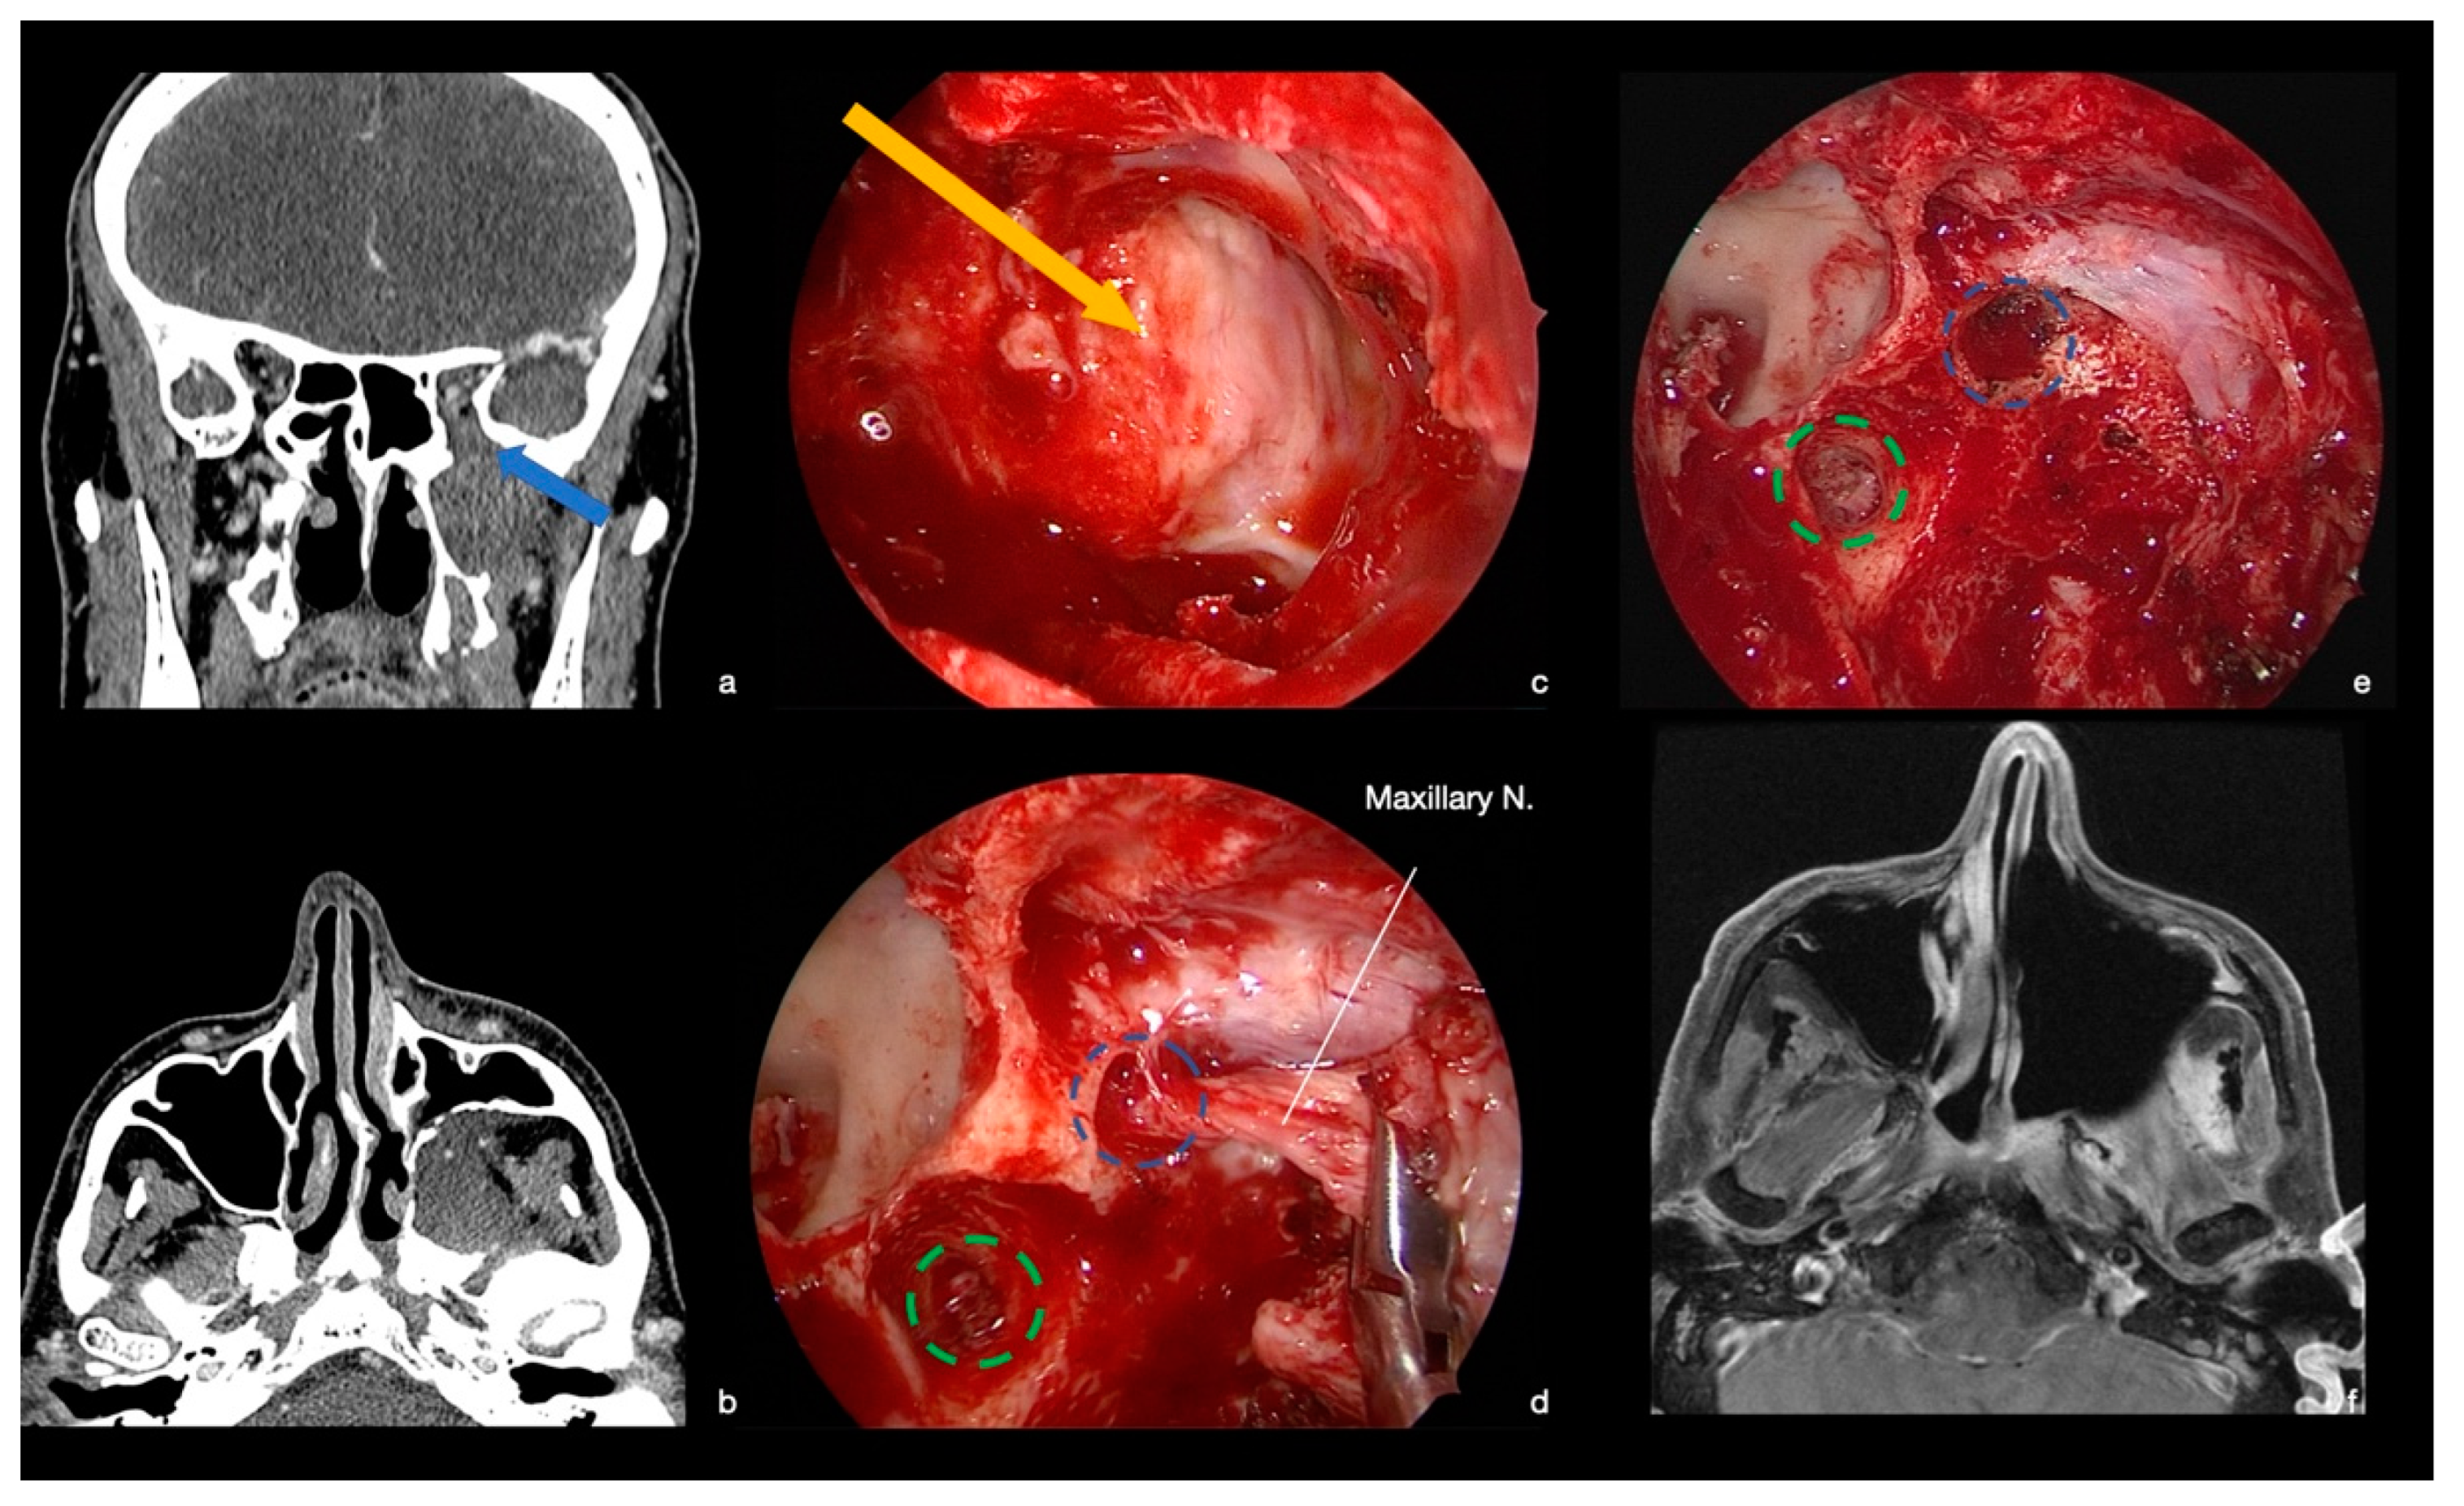

9.2. Case 2